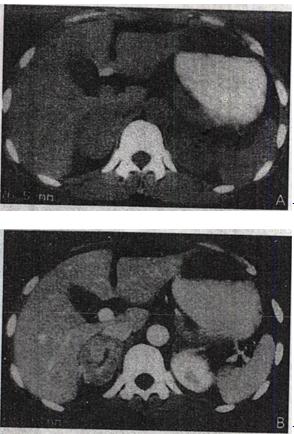

5、 患者,男,2个月。生后发现腹部肿块进行性增大2个月。静脉肾盂造影如图所示。最有可能的诊断是()。

- A、异位肾

- B、重复肾

- C、单肾

- D、马蹄肾

- E、移植肾